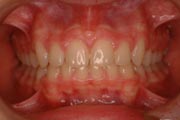

Crowding

Before